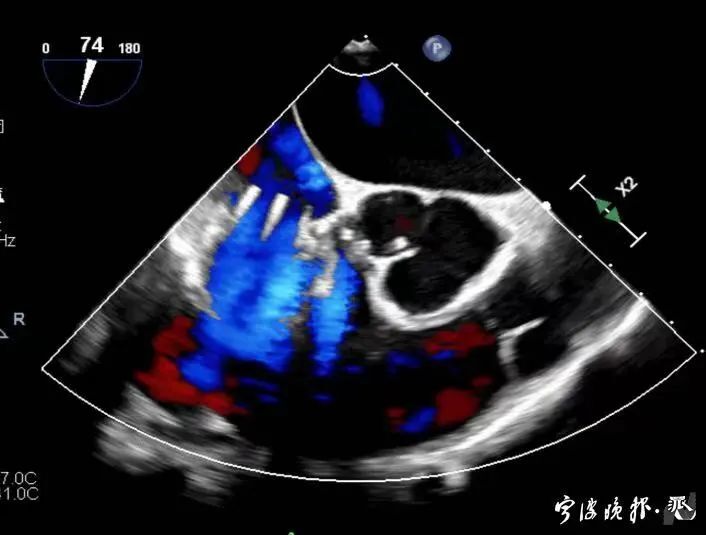

術(shù)前食道心超示三尖瓣重度反流